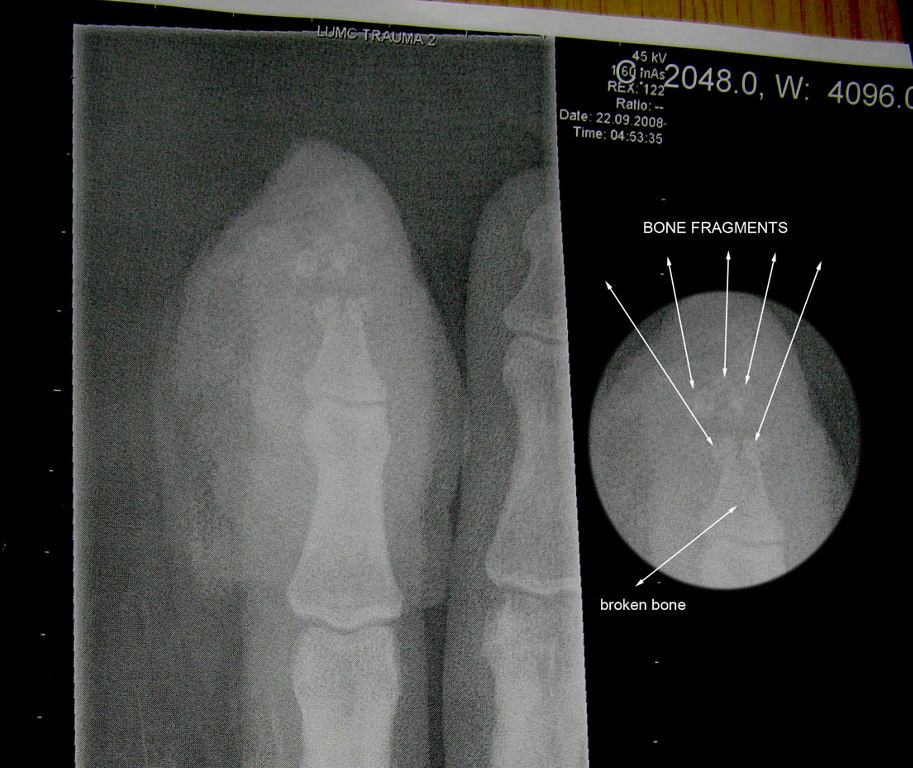

尽管他已经很小心把他们放置在锁住的房间里并相互保持一段距离,但是周日晚当他把他们依次排开把玩,并以为距离挺安全时,他拿起一块翻转了一下,这时距离这块50厘米外的另一块突然自动翻转,极性相吸,瞬时飞过来,他的食指顿时被夹,由于此磁铁吸力太甚,撞击力度大到一下子便把他的食指指尖和指甲夹 夹扁扯断并挤出。后X光显示指尖骨头粉碎,花了一个半小时才取出碎骨。

1.jpg

2.jpg

3.jpg

4.jpg